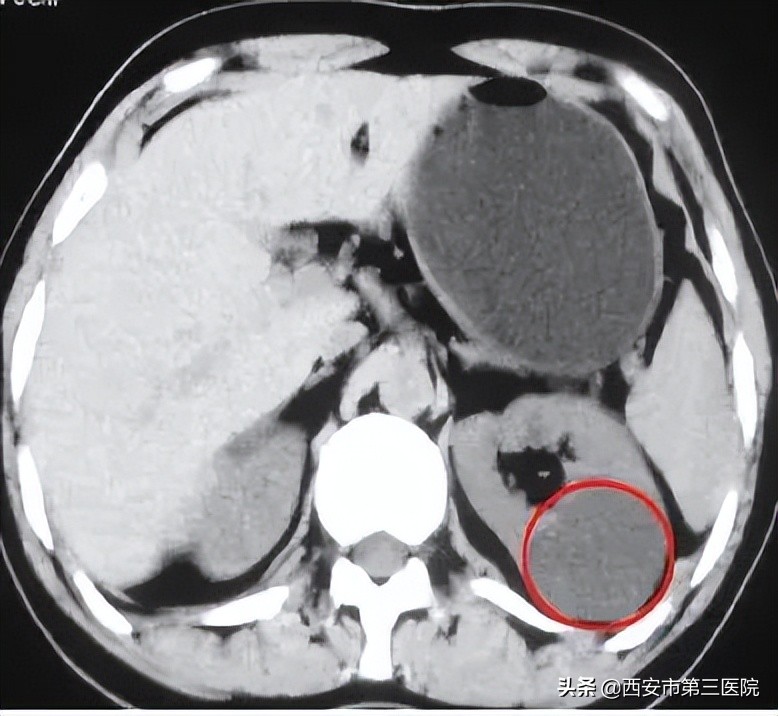

• I级(单纯性):单纯液体密度囊肿,界限清楚,边缘锐利 囊肿壁薄,无分隔、钙化及固体成分。(CT表现)呈水样均质密度,无增强效应。

我们拿这张CT影像图举个例子,肾脏中颜色稍深的部位就是肾囊肿(已用红色圆圈标记出来),我们可以发现这个囊肿内部颜色一致,类圆形,无壁;均匀水样密度灶;边界清晰,边缘光滑锐利,CT无强化表现。增强CT:囊肿内部并无增强组织,也就是说肿瘤内部的组织比较单一,这样的囊肿我们基本可以断定为良性,极少可能为恶性。切除后一般不会复发。